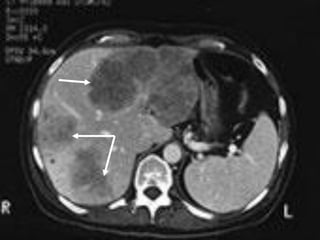

2.3.2.C¸c xÐt nghiÖm th¨m dß h×nh th¸i

■Siªu ©m bông:

+Khèi u: ↓ ©m, ↑ ©m, hçn hîp ©m, quÇng halo

+X©m lÊn TM cöa, TM trªn gan

+D·n ®êng mËt trong gan ë phÝa trªn khèi u

■CT bông cã tiªm c¶n quang

+Tríc khi tiªm c¶n quang: khèi u ↓tû träng, canxi

ho¸ t¹i khèi u, x©m lÊn h¹ch, mµng bông

+Sau tiªm c¶n quang: khèi u ↑tû träng (t¨ng m¹ch

m¸u), x©m lÊn TM cöa vµ TM trªn gan